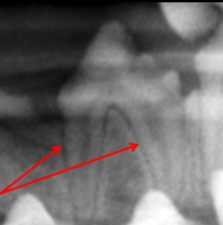

Alveolar Crest

ID

Lamina Dura

Periodontal Membrane